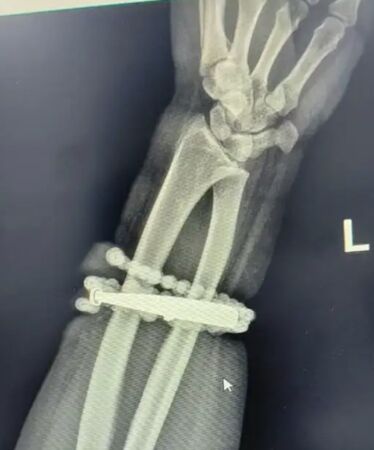

經過一個多小時的手術,醫生成功將手鐲和串珠從厚厚的增生組織中完整剝離出來,並清創引流控制感染。目前,龔女恢復良好,已順利出院。